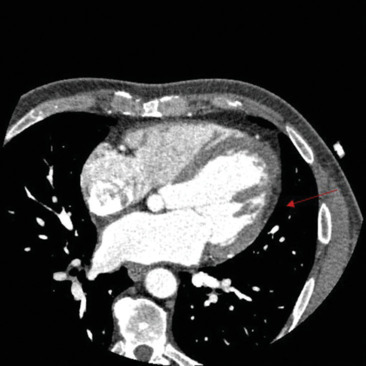

In the evaluation of cardiomyopathies, cardiac computed tomography (CCT) is predominantly used for assessing congenital or acquired coronary artery diseases as a potential etiology underlying the observed myocardial abnormalities. However, its utility is expected to expand. We present a case of an asymptomatic patient with claustrophobia who sought medical attention due to frequent ventricular beats. The resting electrocardiogram revealed repolarization abnormalities characterized by flattened T-waves in the lateral leads and low QRS voltages in the peripheral leads, whereas transthoracic echocardiography was normal. CCT accurately identified hypodense areas indicative of fibrofatty infiltration within the inferolateral and anterior walls of the left ventricle. Furthermore, late iodine contrast-phase imaging revealed subepicardial late enhancement striae in the same regions. These imaging findings were pivotal in establishing a diagnosis of left-dominant arrhythmogenic cardiomyopathy. This clinical vignette underscores the potential of CCT in tissue characterization, particularly when cardiac magnetic resonance imaging is contraindicated or unavailable.

Abstract Image